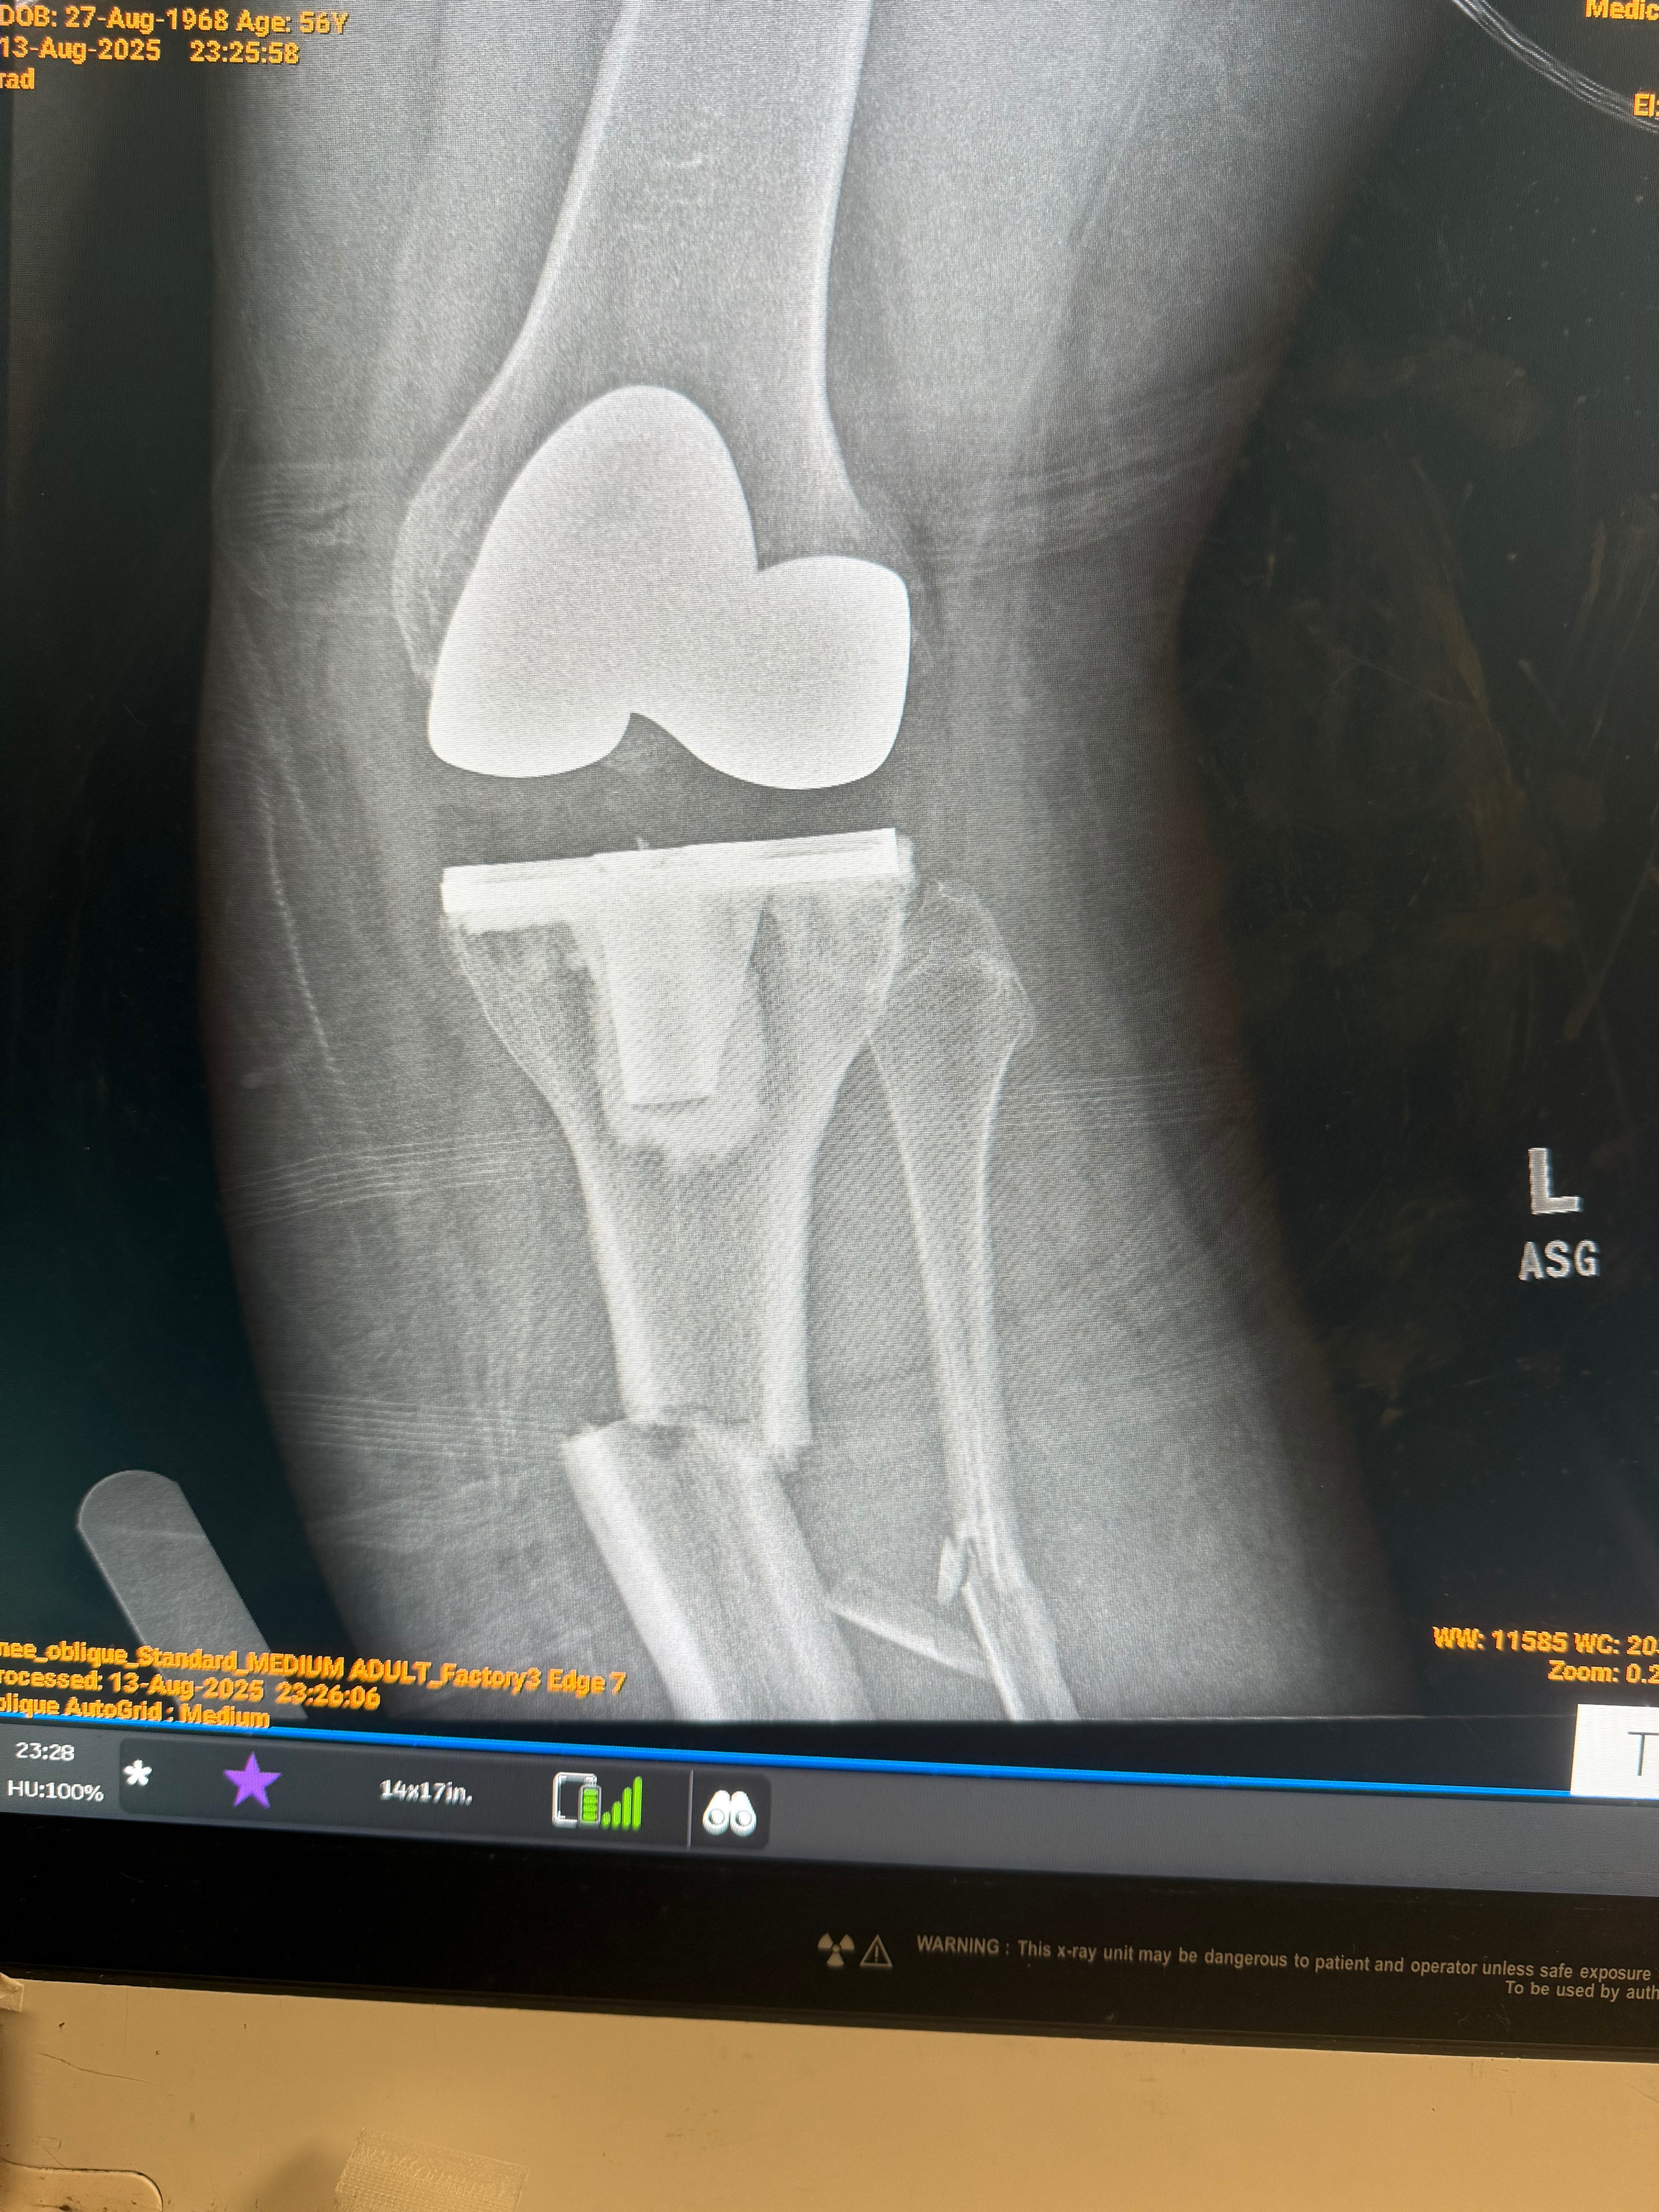

My name is “Suzy” Britz, I’ve spent my life helping others heal, rescuing animals, and as a Texas Realtor, guiding families and investors to build wealth. Now, I find myself on the other side, in urgent need of support. After a sudden fracture on August 13th left my tibia broken in half, I’ve been unable to walk or work. This injury, along with past orthopedic conditions and a misaligned knee replacement, has left me facing multiple surgeries and months of rehabilitation.

My savings are gone, and emergency SSDI does not cover my rent, medical care, or the accessibility modifications I need to recover safely. I urgently need help with housing, utilities, medical co-pays, physical therapy, transportation, and accessibility equipment. I am currently in therapy twice a week to gain enough strength for two critical surgeries: a total left knee replacement and a revision to a hinged knee replacement.